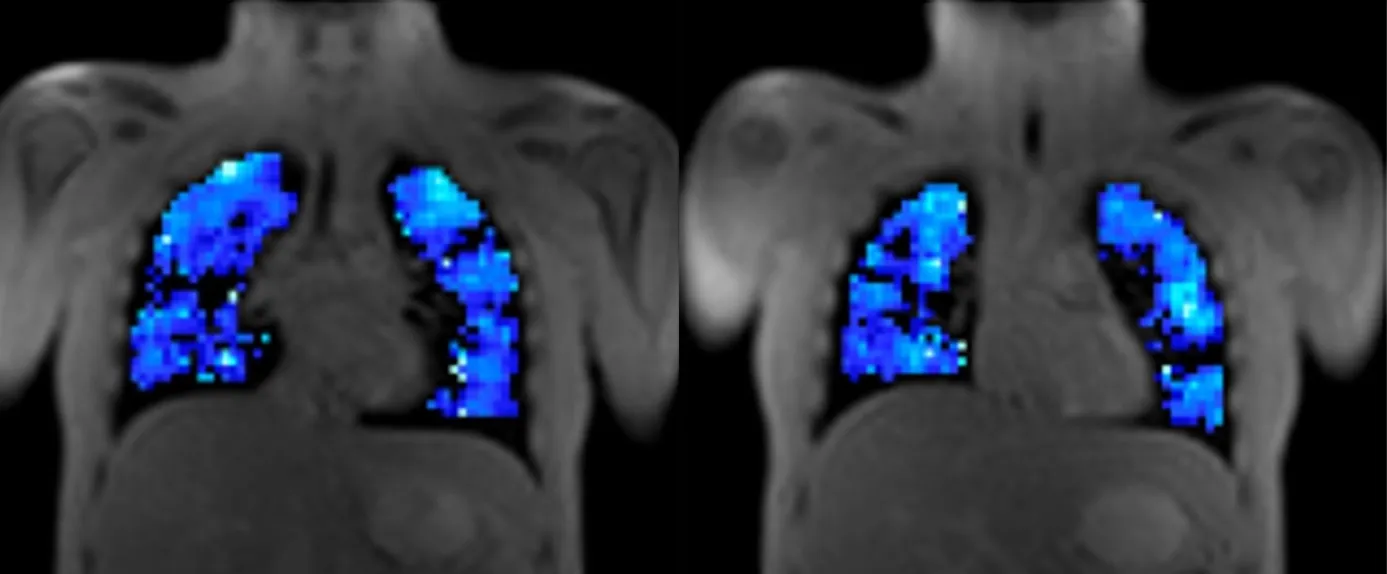

The images show ventilation maps from different coronal slices in an adult cystic fibrosis patient. Blue indicates regions receiving oxygen; black regions indicate defects.

Lung OE-MRI monitors the delivery of oxygen to patient's lungs. The acquired quantitative imaging biomarkers relate to regional lung ventilation and gas diffusion. Bioxydyn has extensive experience in deploying OE-MRI in diseases including chronic obstructive pulmonary disease (COPD), cystic fibrosis, Primary ciliary dyskinesia (PCD), interstitial lung disease (ILD), lung cancer, and asthma.